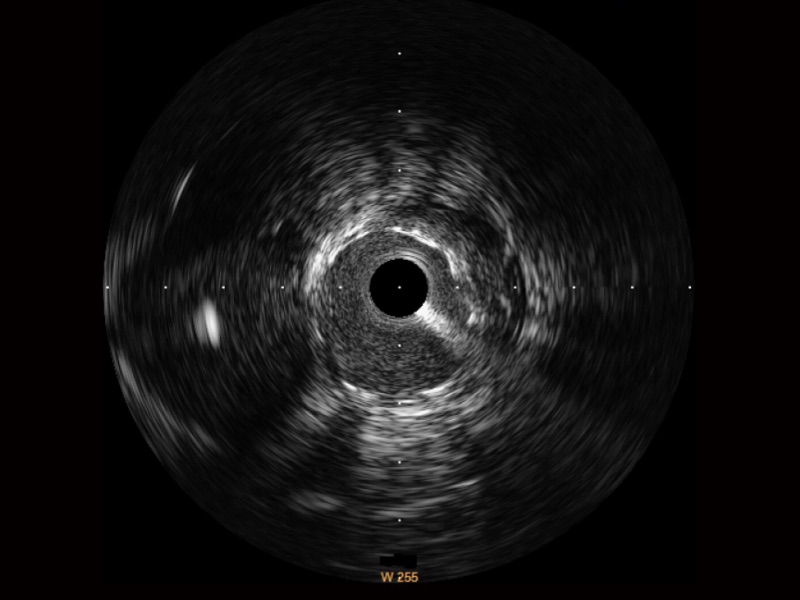

• 传统IVUS图像

对比传统IVUS导管成像,玖鼎集团宽频IVUS图像的近场支架梁显影更细腻,远场中膜外血管仍清晰可辨,兼顾远中近,兼顾分辨力与穿透深度